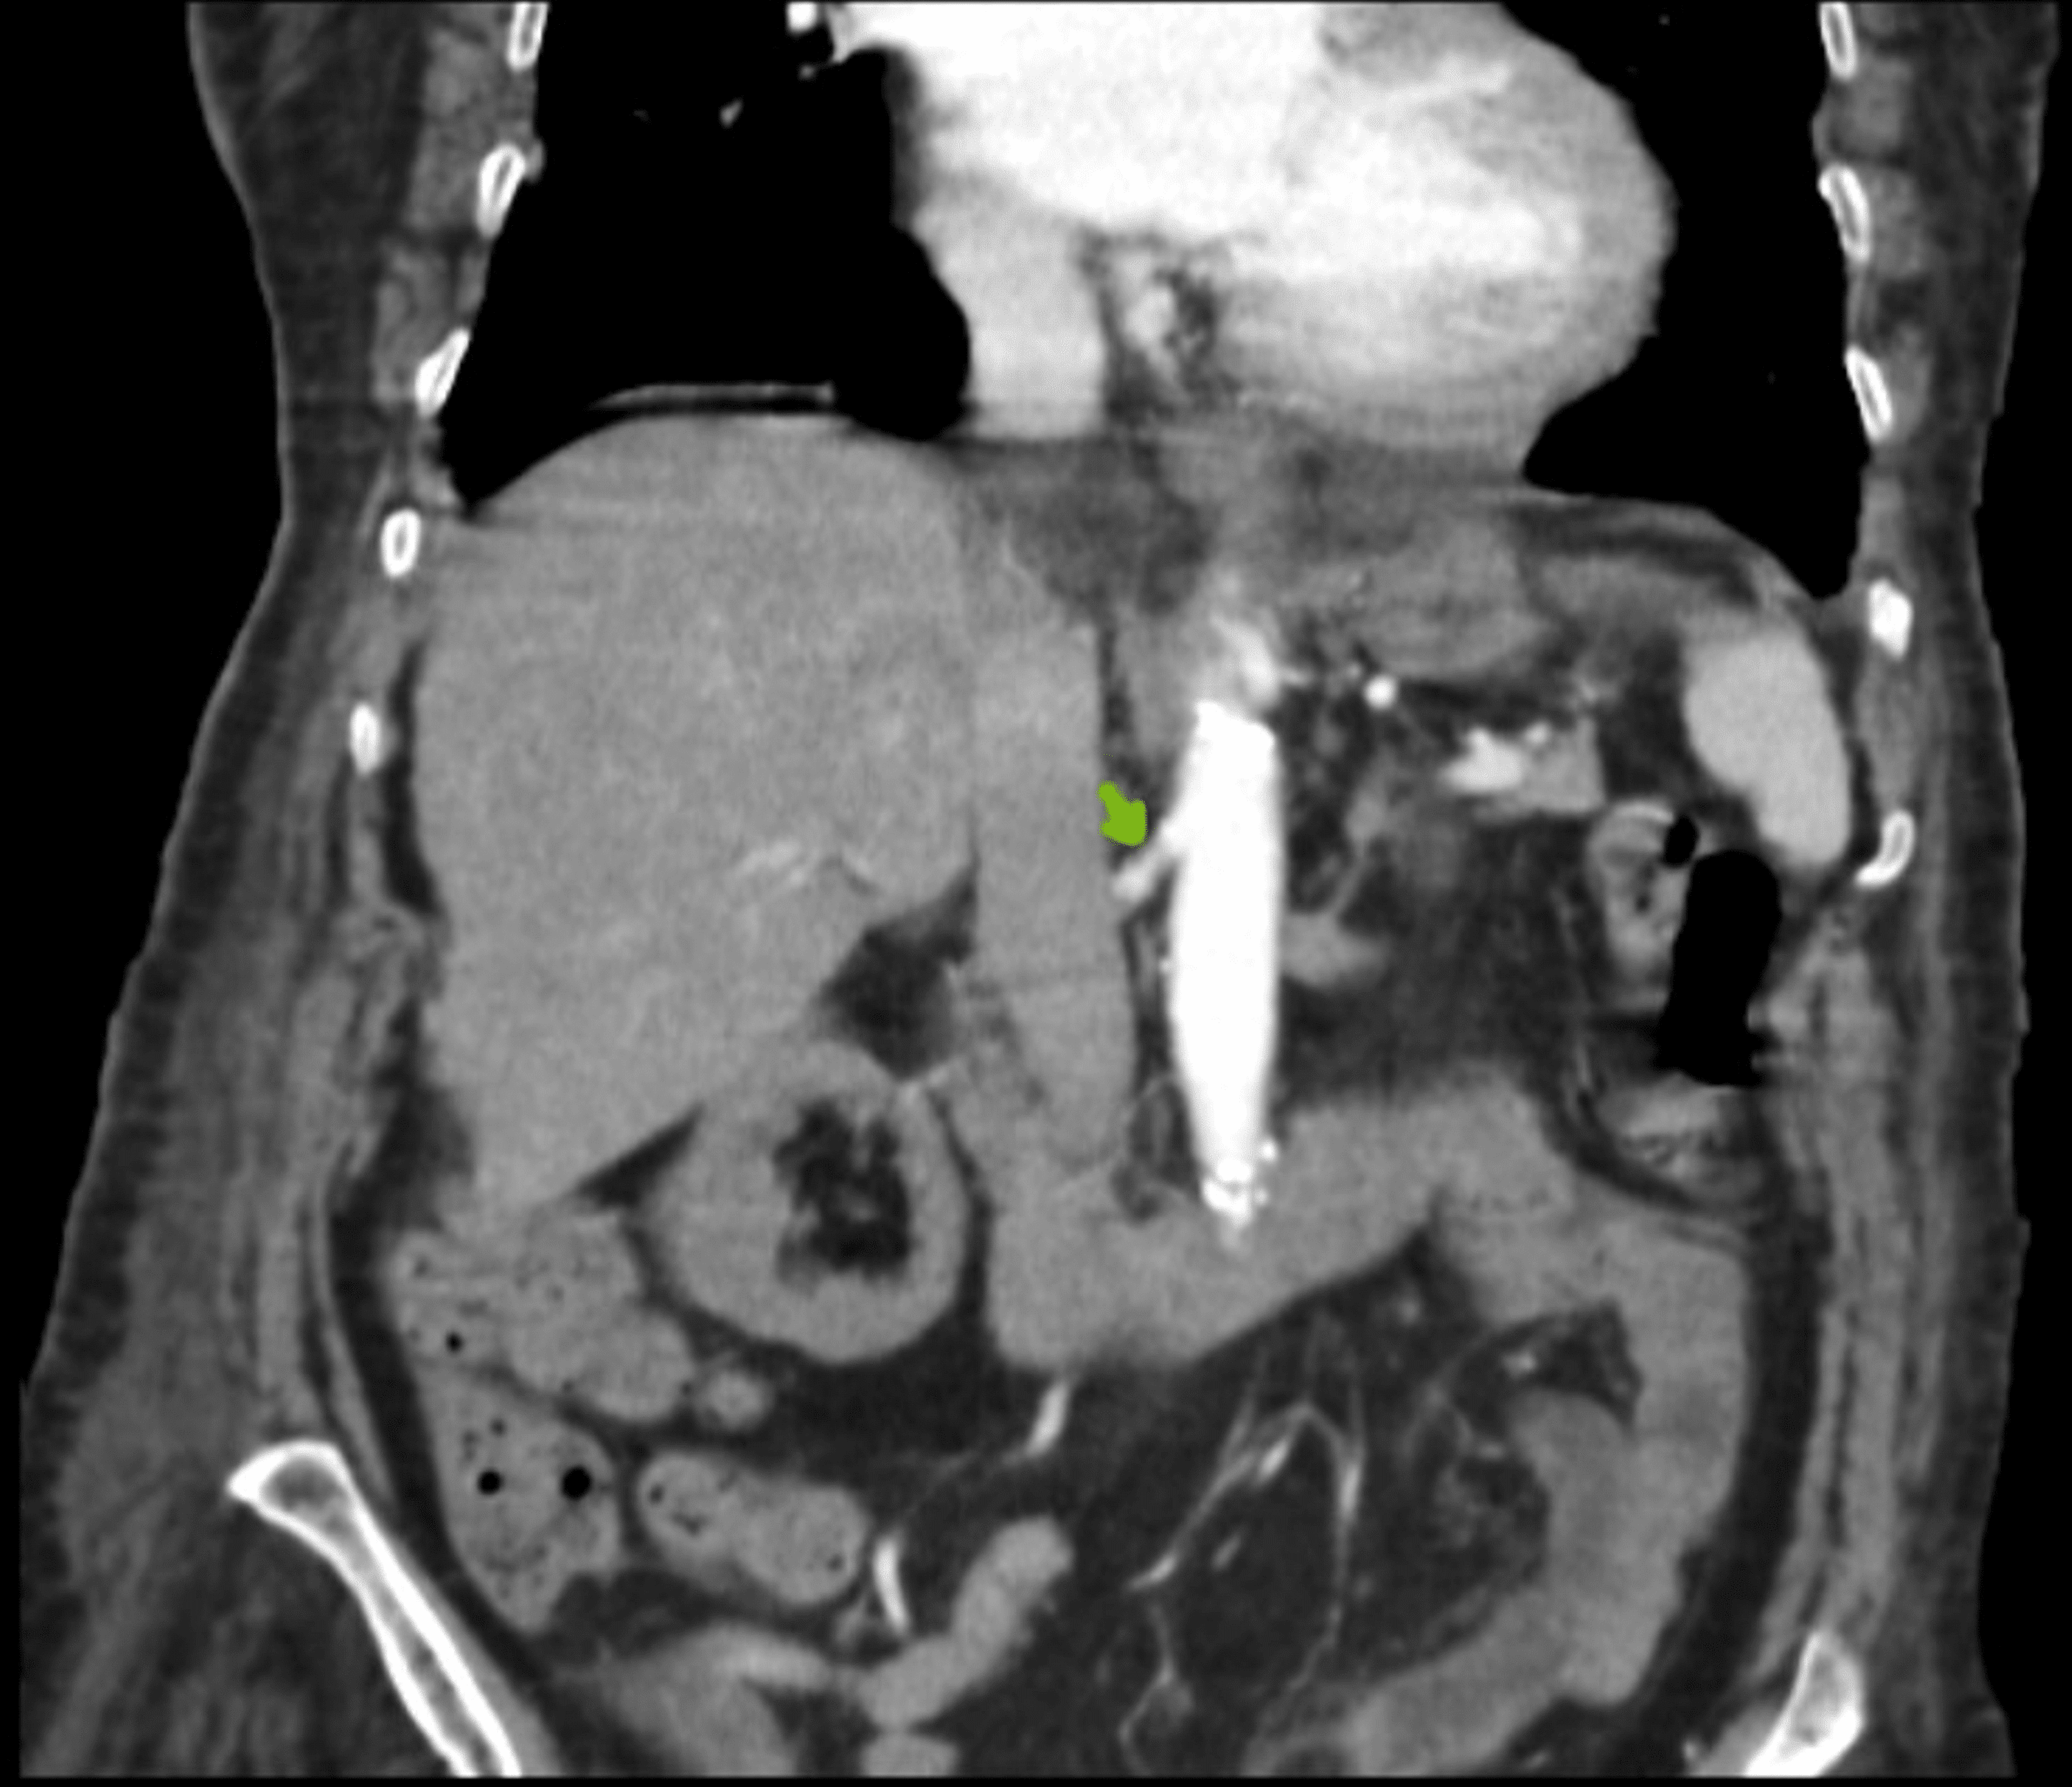

Figure 3 CT scan showing left renal artery thrombosis (white asterisk

Figure 3 CT scan showing left renal artery thrombosis (white asterisk Case Report Renal Artery Thrombosis  To the best of our knowledge this. Web  in this case report, the authors review a case of renal infarction caused by renal artery thrombosis in a patient with risk. Web in this case report, the authors review a case of renal infarction caused by renal artery thrombosis in a patient with risk factors for. Case Report Renal Artery Thrombosis.